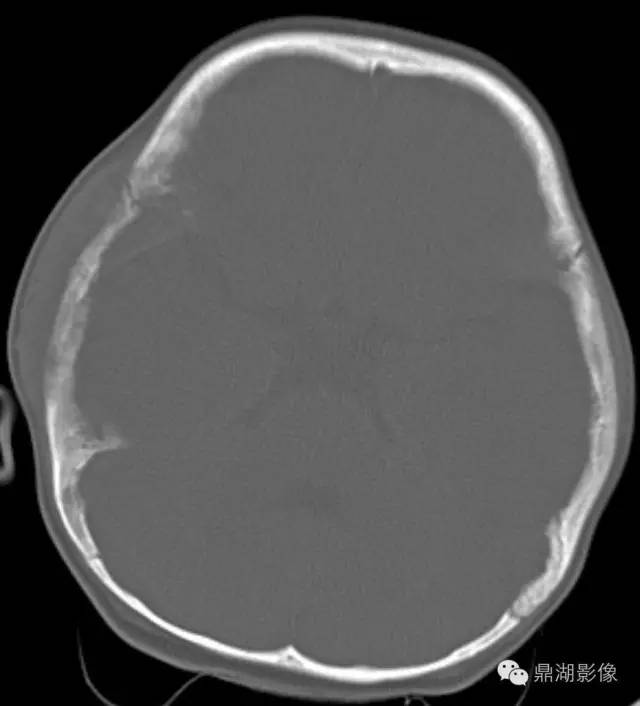

70岁,男,前列腺癌患者

X线片表现:成骨性转移表现为在骨外型没有改变的骨背景上出现圆形或椭圆形致密影,有时呈地图状,边缘不规则,多数病灶可融合成片,也有病灶累及大部分或整个骨,有时在成骨性病灶边缘散在少量溶骨性破坏。密度呈棉絮样增高。前列腺癌骨转移多较典型,结合临床,诊断一般不难。

实验室检查,血清碱性磷酸酶常增高,约占80%~85%;血清酸性磷酸酶也明显增高,对诊断前列腺癌骨转移有重要价值。